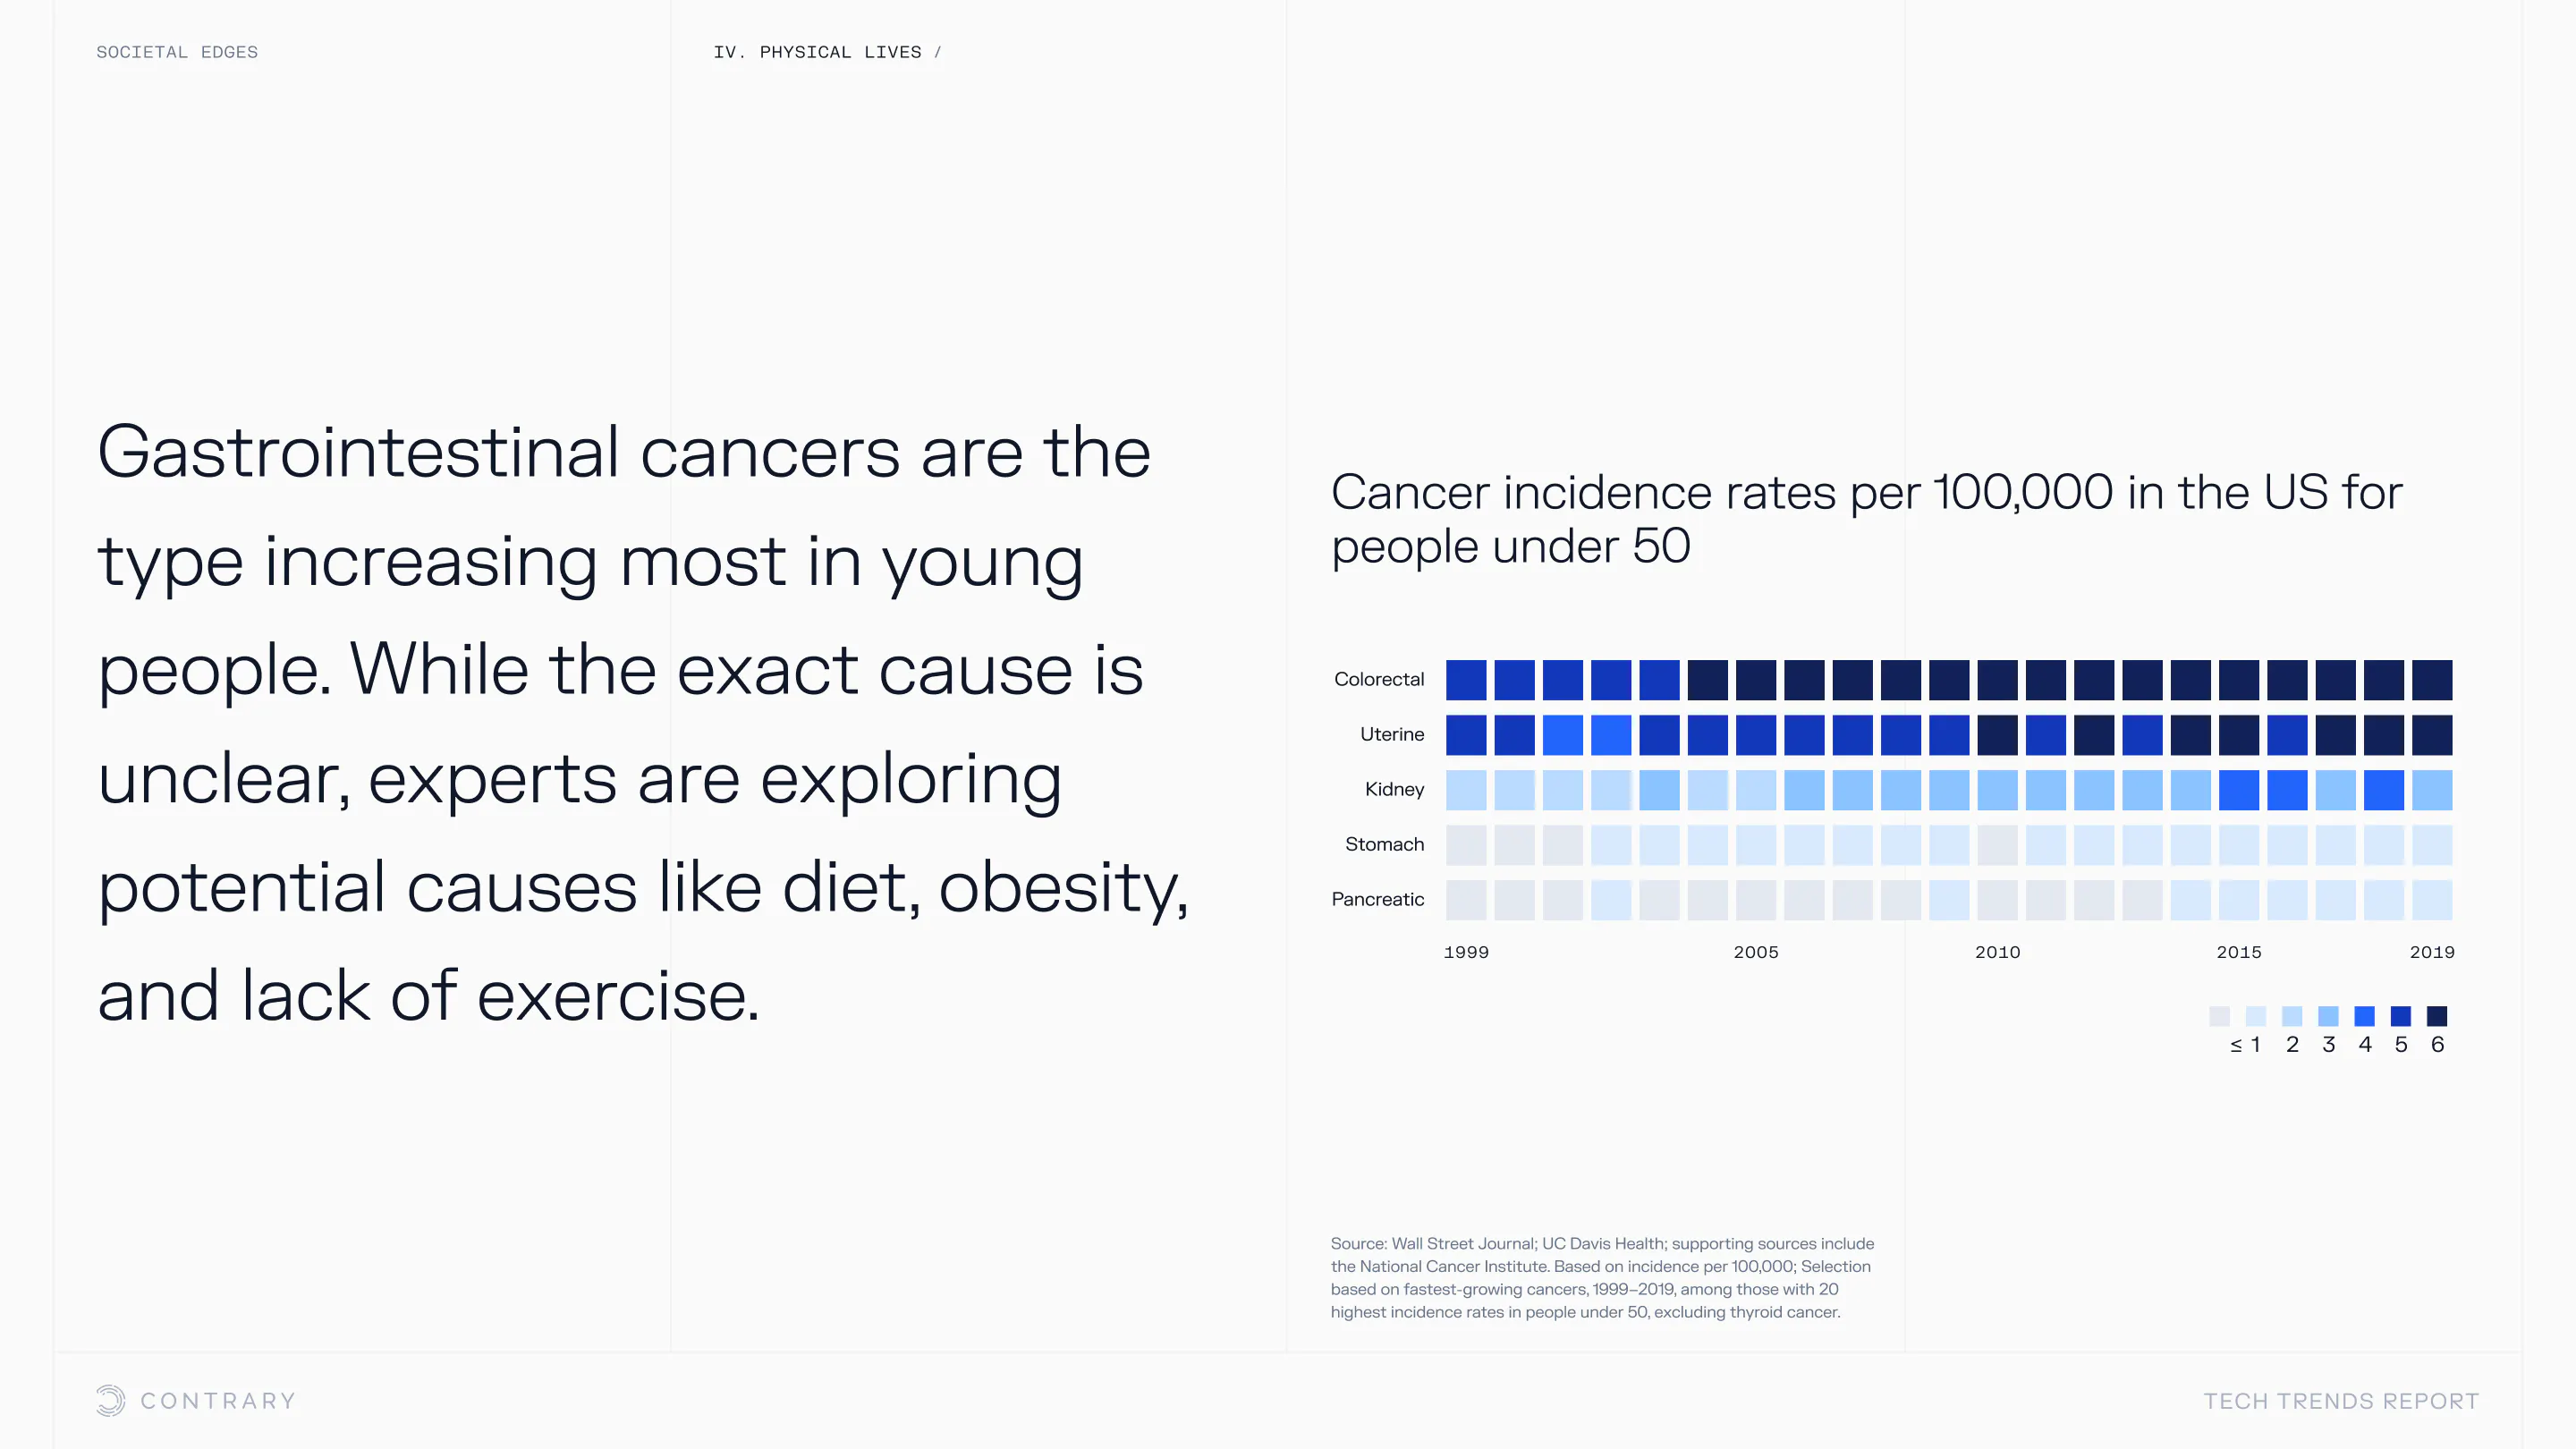

An aging population is bringing up a range of increased concerns, from mental health to disease control. Obesity and gastrointestinal cancers are plaguing younger generations. The cutting edge is tackling a system that has unhealthiness woven into it.